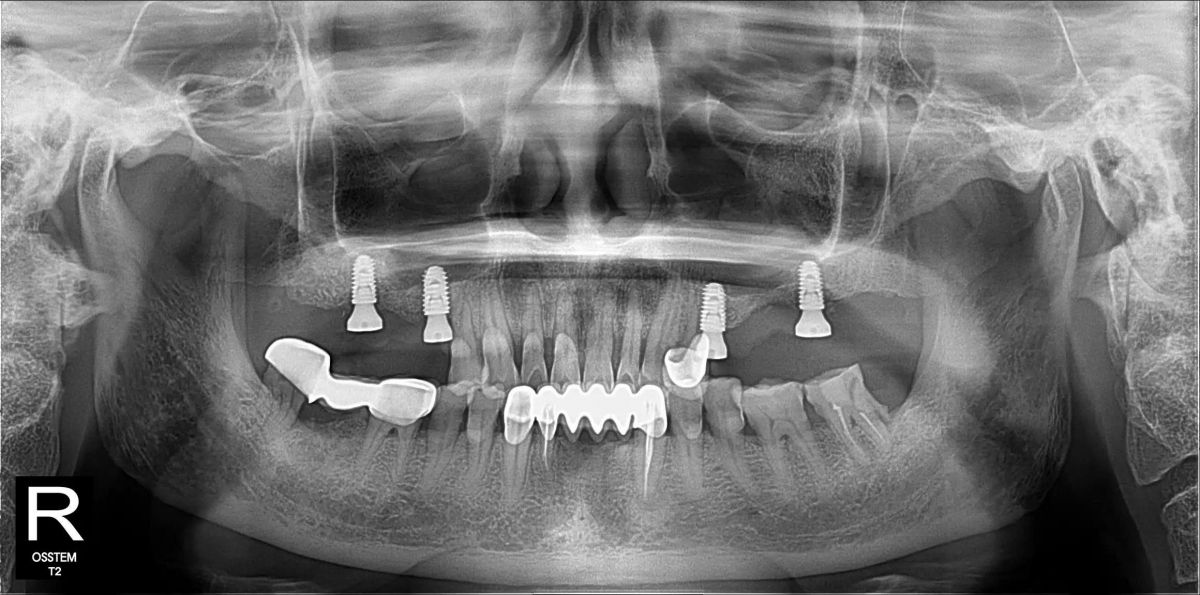

Kết quả chuẩn đoán từ phim 3D

Qua chụp CT ConeBeam 3D, bác sĩ ghi nhận chú Hòa mất toàn bộ răng hàm trên hai bên:- Mất răng R15, R16, R17 (hàm phải)

- Mất răng R25, R26, R27 (hàm trái)

- Tiêu xương nghiêm trọng

- Xoang hàm hạ thấp

- Không đủ xương để cấy Implant trực tiếp

Sau khi đánh giá tổng thể và lập kế hoạch điều trị bằng công nghệ Hansafe, bác sĩ quyết định thực hiện phác đồ như sau:- Hàm phải: Implant tại R15 – R17, phục hình 3 răng, nâng xoang kín hàm phải

- Hàm trái: Implant tại R25 – R27, phục hình 3 răng, nâng xoang hở hàm trái